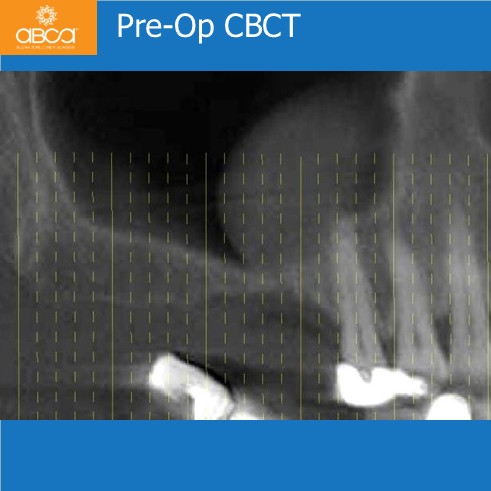

Categories3-6 Months, Augma Bone Cement Academy, Augma Lift™, Bond Apatite®, Bone Cement Expert, Clinical Cases, Closed Sinus Lift, Images, Kit A, Post-Op Period, Sinus Lift, Upper Right Molar March 2, 2026 Sinus Lift with Augma Lift™ Kit A – Missing Tooth #16 (3) Less than 2 mm of sub-sinus bone height Post navigationPrev Rehabilitation of the Left Maxilla, with Immediate Implant Placement Next Augma Simplified Webinar Leave a Reply Cancel replyYou must be logged in to post a comment.